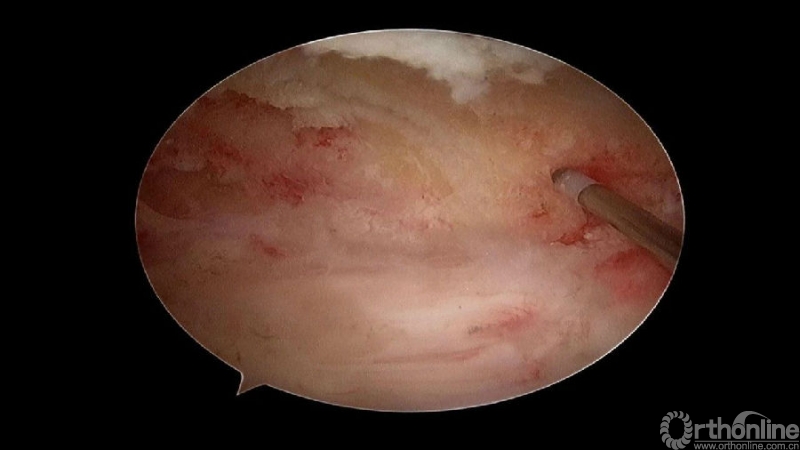

3.从游离骨块的背侧开始,用磨钻将骨块打薄,然后将骨块的底面与脊髓表面仔细分离,将游离骨块摘除;

4.进一步加深移除骨赘的残余部分,直到显露出对侧的神经根及关节突关节的内壁;